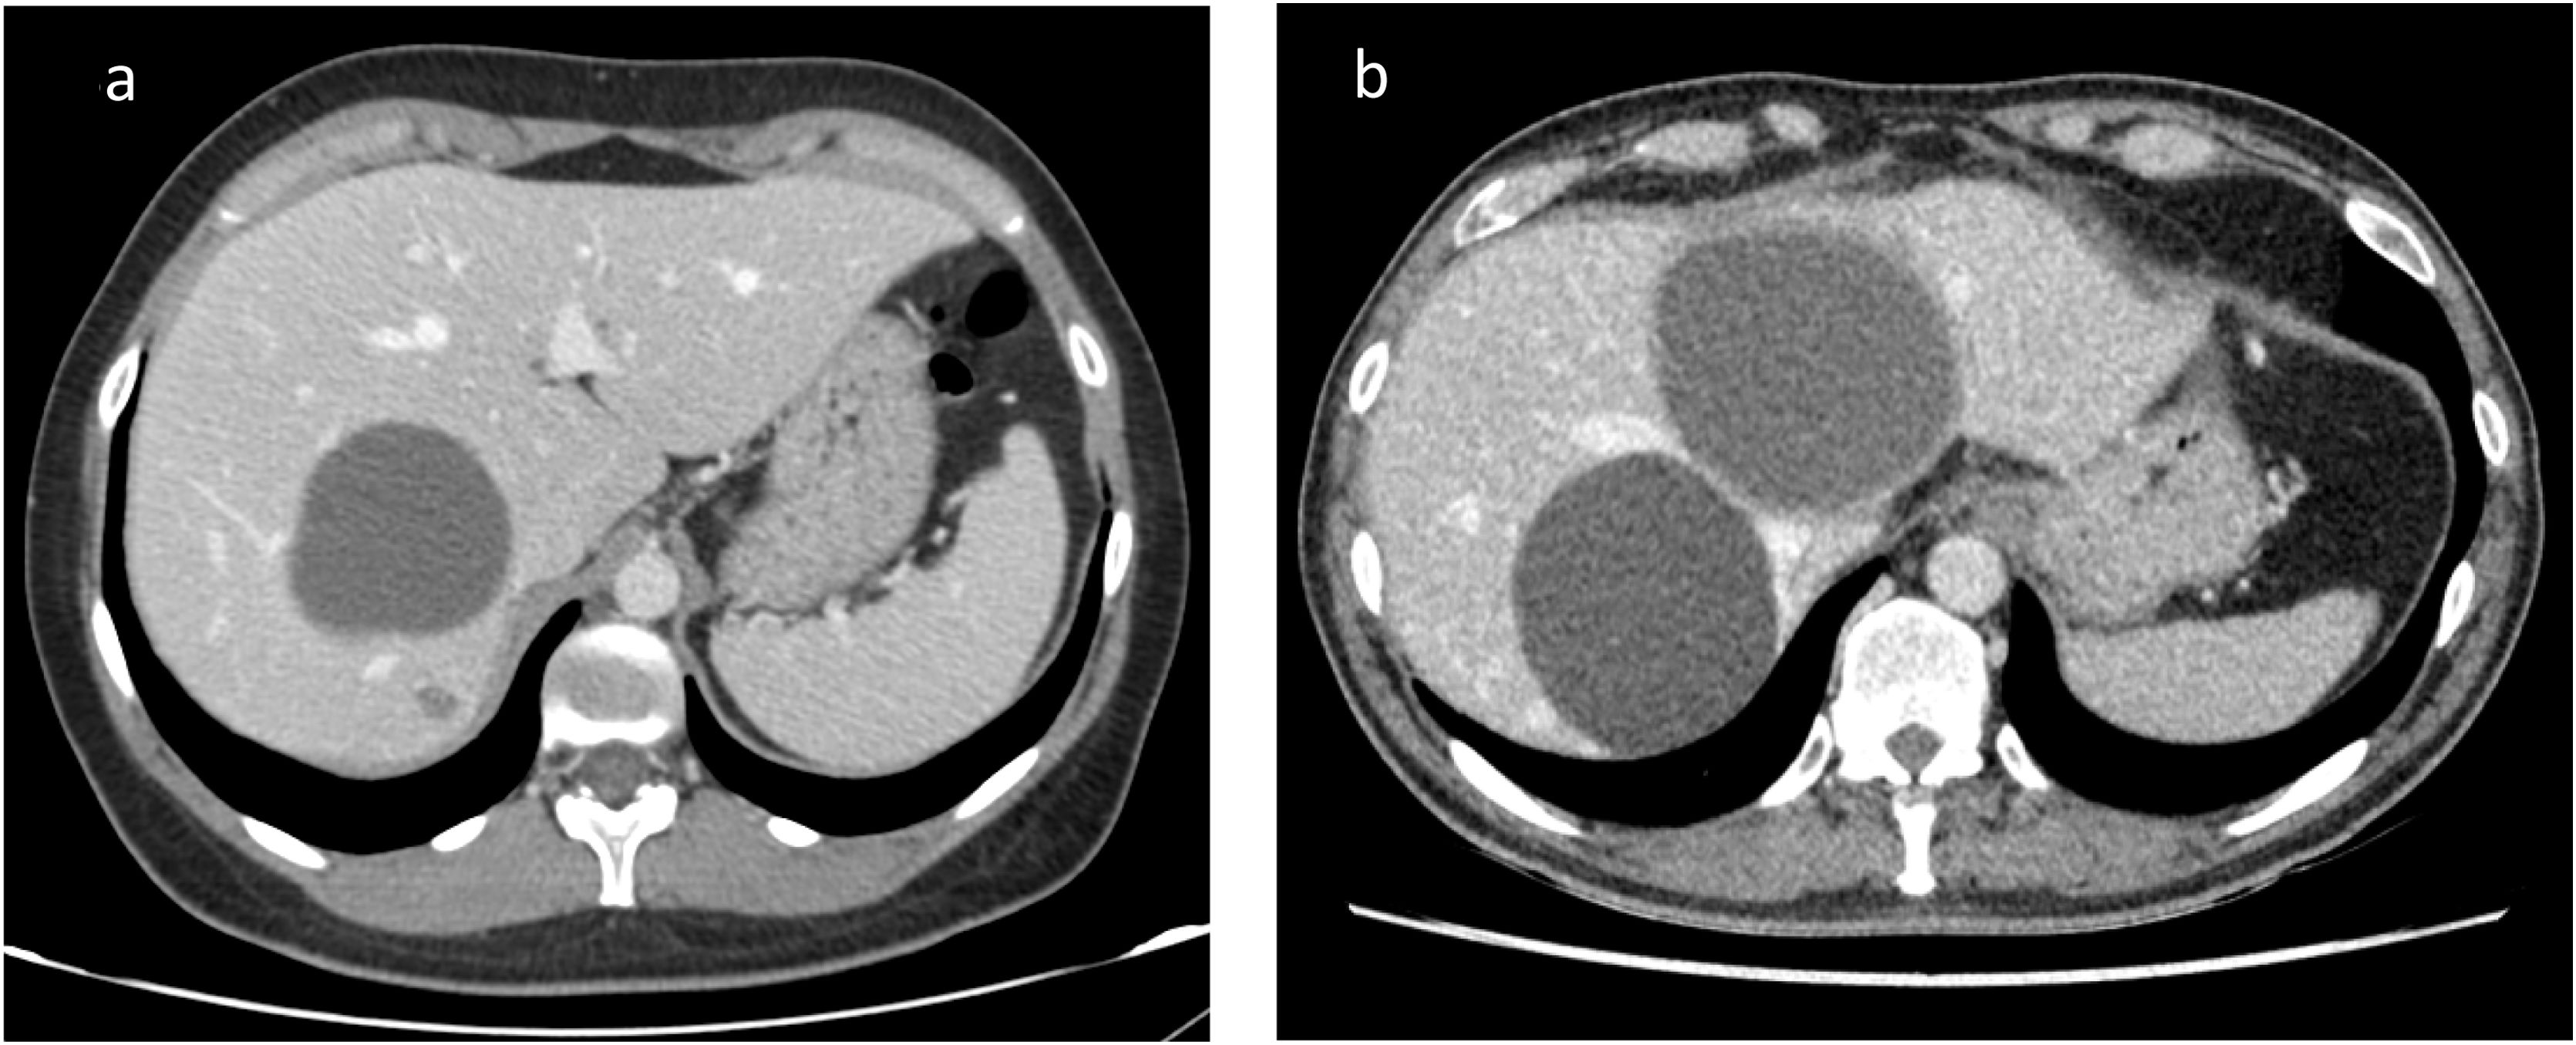

En la mayoría de las ocasiones, los quistes hepáticos no producen síntomas y se descubren de forma casual al realizar alguna exploración del hígado por otro motivo (generalmente una ecografía o una tomografia axial computarizada o TAC). Existen varios tipos de quistes hepáticos.

Los más frecuentes, con gran diferencia, son los quistes simples, que son benignos, de pared fina y de tamaño variable. La mayoría de ellos son de pequeño tamaño y no producen síntomas ni otros problemas. Son más frecuentes en mujeres y la gran mayoría no requiere seguimiento ni tratamiento.

En algunas ocasiones, bastante más raras, estos quistes pueden ser de gran tamaño (por encima de los 5 cm) o menos grandes pero numerosos, y entonces pueden provocar algunos síntomas como, por ejemplo, molestias abdominales, sensación de saciedad u otros. De forma infrecuente, estos quistes grandes se pueden complicar: si sangran, si se torsionan, si se rompen o si comprimen alguna otra estructura vecina, como por ejemplo la vena porta.

Otras veces, lo que ocurre es que hay múltiples quistes en el hígado. Se trataría de la enfermedad poliquística del hígado, definida por la presencia de cuatro o más quistes. Es una entidad infrecuente y algo peculiar, ya que es hereditaria; la afectación del hígado es más importante y frecuentemente se asocia con quistes en otros órganos como el riñón (la más frecuente, que puede causar insuficiencia renal), el bazo o el páncreas, así como alteraciones a otros niveles, por ejemplo, aneurismas intracraneales. Al ser hereditaria, es necesario estudiar a la familia.